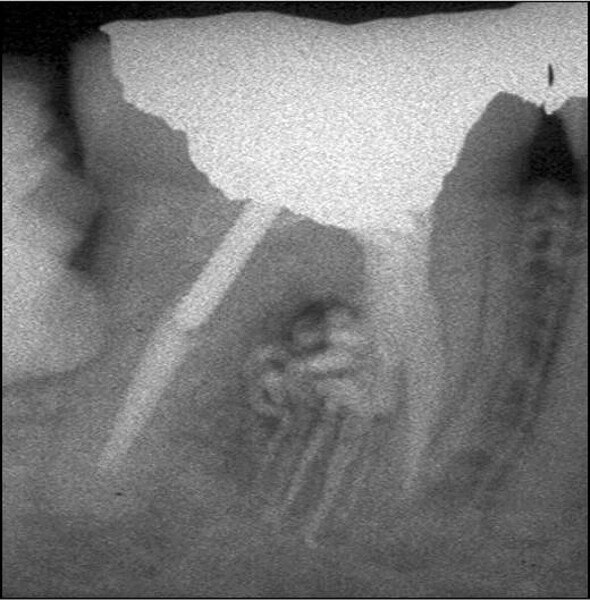

Buccal root of the bifurcated maxillary premolar—a danger zone during root canal therapy